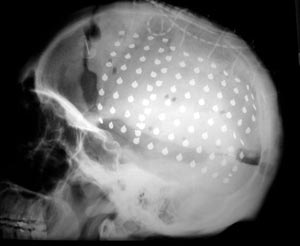

Figura 94 - Radiografia obtida após a cirurgia demonstrando as placas subdurais implantadas.

Figura 98 - Radiografia obitda após a cirurgia demonstrando as placas subdurais implantadas.